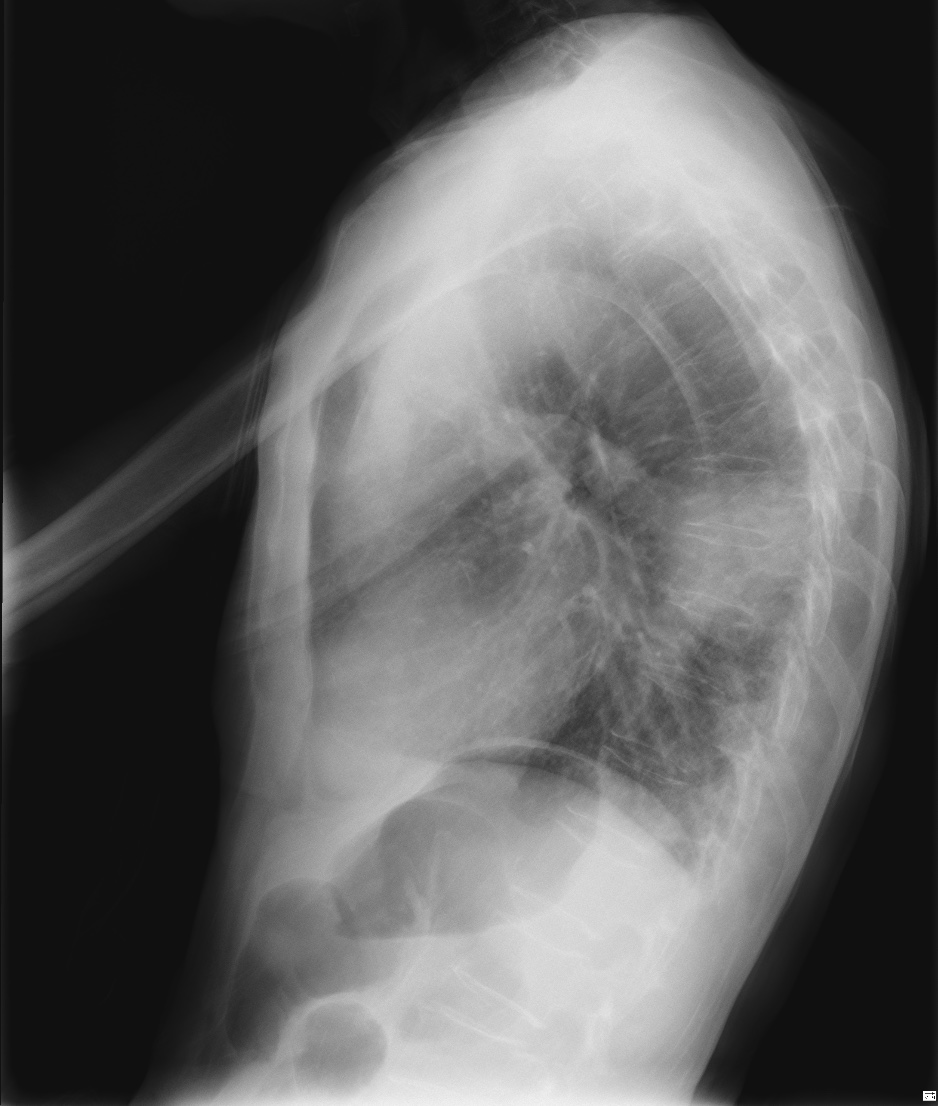

CASO: Febrícula y tos de 4 días de evolución.

Hallazgos:

- En la placa PA se observa una asimetría en los hilios pulmonares, el hilio izquierdo tiene una densidad aumentada.

- Tras examinar la placa lateral se observa un aumento de densidad en la columna que puede ser compatible con una condensación, es el signo de la desnificación vertebral.

SIGNO DE LA DENSIFICACIÓN VERTEBRAL: En la radiografía lateral normal, la densidad de la columna torácica tiende a disminuir desde la parte superior hasta el diafragma; la alteración de ese patrón por la presencia de una densidad superpuesta a la columna, indica la existencia de una consolidación pulmonar. Este signo adquiere especial valor cuando en la proyección posteroanterior la consolidación está oculta en el espacio retrocardíaco o en la base pulmonar.